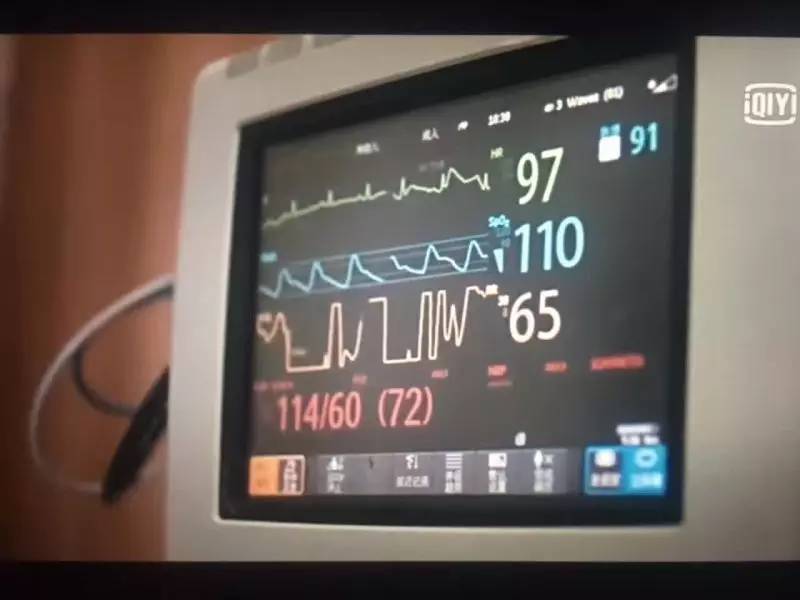

ICU里的“魔肺”

ICU并不可怕

ICU为什么这么贵

ICU为什么不让陪护